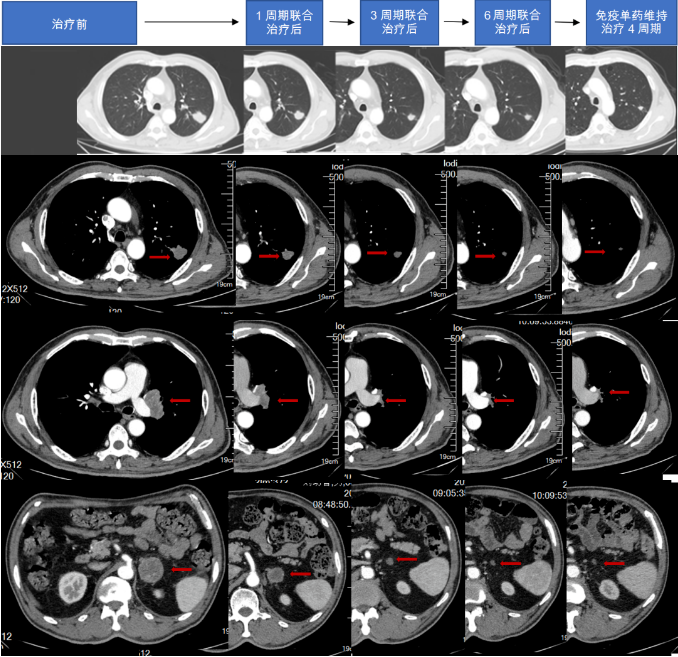

2022-08-13、09-08、09-30、10-24、11-15、12-10行斯鲁利单抗300mg D1+依托泊苷100mg D1-5+顺铂30mgD1-4 Q3W方案治疗6周期。

2023-01-04、01-30、02-21、03-18斯鲁利单抗单药300mg Q3W维持治疗4个周期。

综合治疗1周期影像学报告(2022-09-07):结合病史,1、肺Ca复查,左肺上叶占位并左肺门多发肿大淋巴结,较前(2022-08-08)减小;双侧肾上腺占位,较前减小;腹膜后淋巴结转移,较前略减小;左侧颈部淋巴结转移,部分较前减小,请结合临床并复查。2、双肺肺气肿,多发肺大泡;双肺下叶少许炎症;左肺下叶钙化灶3、主动脉壁及冠状动脉壁钙化斑块。

综合治疗3周期影像学报告(2022-10-23):结合病史,肺Ca复查,左肺上叶占位,较前(2022.09.07)减小,左侧肺门淋巴结较前缩小;左侧肾上腺占位,较前减小;腹膜后小淋巴结,较前变化不著;左侧颈部淋巴结转移,较前减小。2、双肺肺气肿,多发肺大泡;双肺下叶少许炎症;左肺下叶钙化灶3、主动脉壁及冠状动脉壁钙化斑块。

综合治疗6周期影像学报告(2023-02-02):结合病史,肺Ca复查,左肺上叶占位,较前(2022.10.23)变化不著;左侧肺门淋巴结较前略缩小;左侧肾上腺占位,较前似略有减小;腹膜后小淋巴结,较前变化不著;左侧颈部淋巴结转移,较前减小2、双肺肺气肿,多发肺大泡;双肺下叶少许炎症;左肺下叶钙化灶3、主动脉壁及冠状动脉壁钙化斑块。

2023-03-18影像学报告:结合病史,肺Ca复查,左肺上叶占位,较前2023.02.02变化不著;左侧肺门淋巴结较前变化不著;左侧肾上腺占位,较前变化不著;腹膜后小淋巴结,较前变化不著;左侧颈部淋巴结转移,较前变化不著2、双肺上叶磨玻璃小结节,左肺下叶实性小结节,较前变化不著。3、主动脉壁及冠状动脉壁钙化斑块。

图4.治疗后胸腹部CT

依据2022年CSCO指南,于2022年8月13日开始行斯鲁利单抗联合依托泊苷、顺铂治疗,用药1周期后停用降颅压药物无头晕头痛,可独立行走,语言功能恢复正常,肿瘤标志物明显下降,CT显示原发灶及淋巴结明显缩小。联合治疗1周期后疗效达到PR。肿瘤标志物1周期恢复正常。6周期联合治疗后,斯鲁利单抗单药维持治疗期间,肿瘤标志物稳定,影像学显示肿瘤持续缩小,且无新发病灶。患者一线PFS已达8个月,且在整个治疗过程中,患者未出现明显免疫相关不良反应(irAE),安全性良好。此案例显示,斯鲁利单抗在ES-SCLC有症状脑转移及PS评分差的患者中,仍显示出持久抗肿瘤效果,为ES-SCLC一线治疗提供新的方案选择。